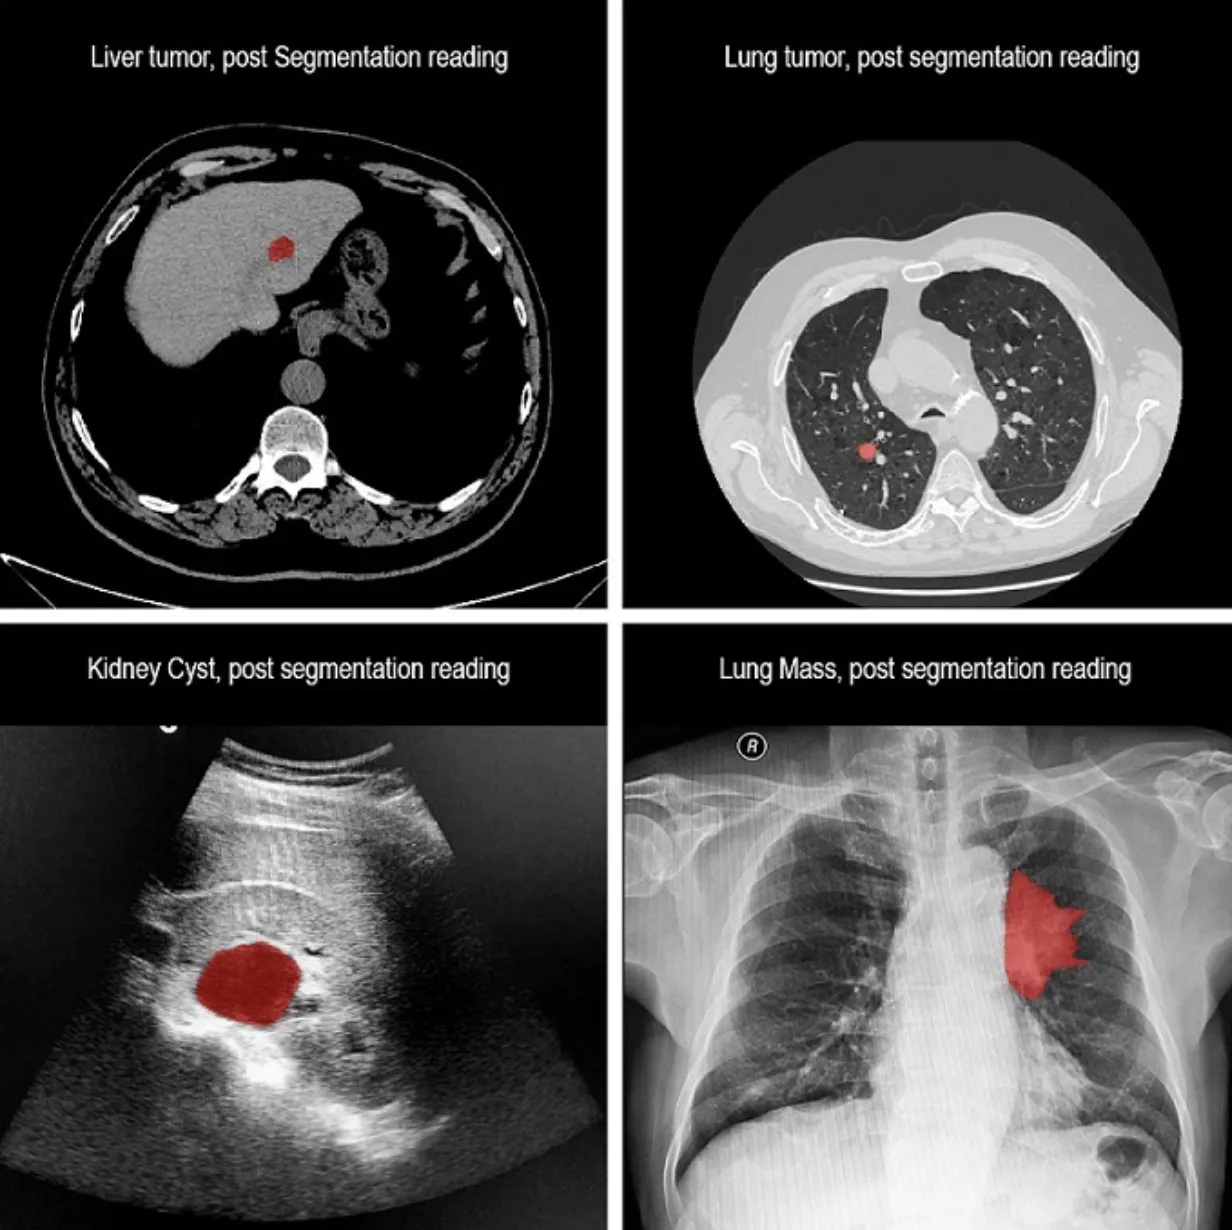

Medical data processing (for example, segmentation of MRI images searching for tissues, tumors, anomalies, and their characteristics such as area, dynamics, etc.);

Source